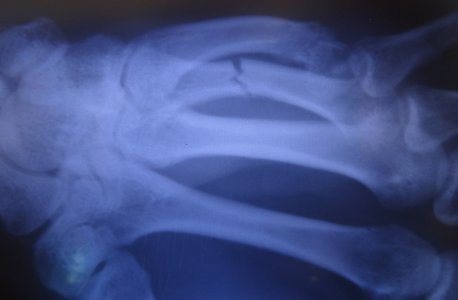

Доктор взглянув на НЕЗНАЧИТЕЛЬНОЕ СМЕЩЕНИЕ сказал что нужна репозиция, сделал закрытую репозицию отломков и наложил лонгету на 4 и 5 пальцы в вытянутом состоянии, вот снимки сразу после наложения лонгеты:

Сказал ходить 5 недель + кальцемин 2 р. в день и контрольный снимок через 7 дней, вот он: